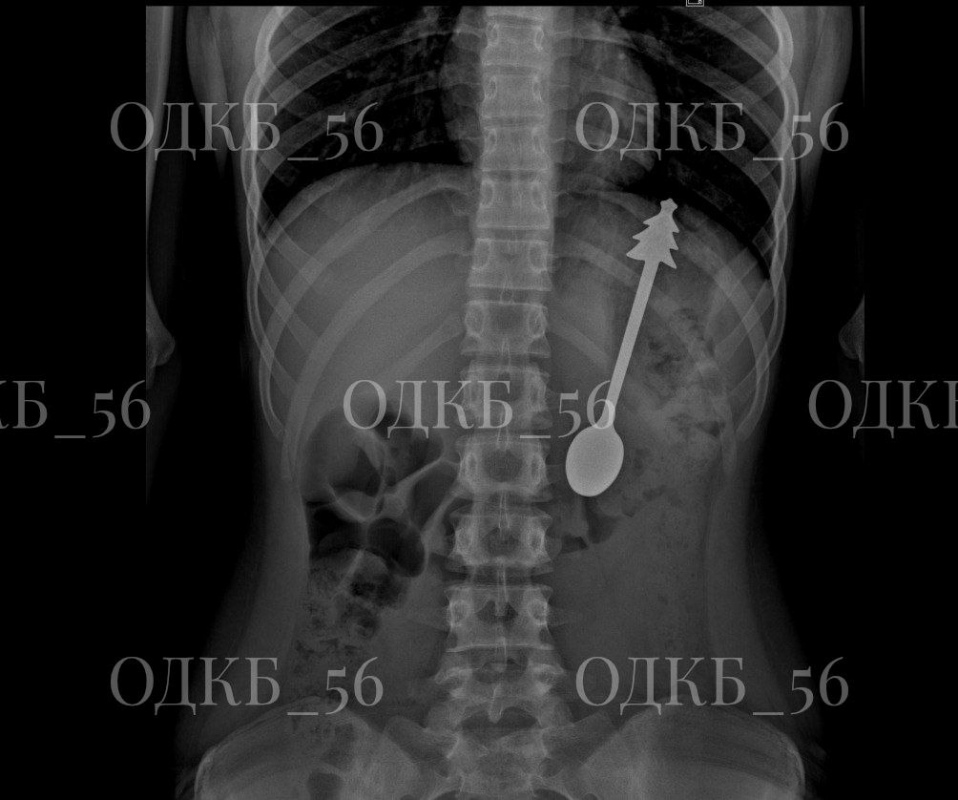

В приёмном отделении ОДКБ экстренно провели рентгенографию органов брюшной полости. В проекции желудка было выявлено инородное тело. Ребёнка госпитализировали в детское хирургическое отделение № 1.

В экстренном порядке, под общим обезболиванием, специалисты выполнили эзофагогастродуоденоскопию и эндоскопически удалили инородный предмет – металлическую ложку длиной 14 сантиметров.